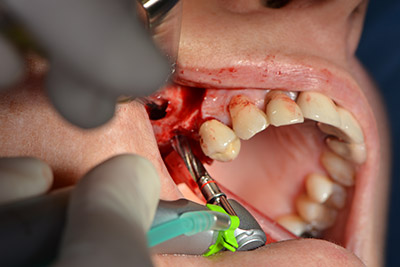

Следващата стъпка е синус лифт с непосредствено имплантиране. Implantmed е предварително настроен на първа позиция за букална фенестрация на стената на максиларния синус.

Фенестрацията е извършена при 35,000 rpm и след това носната лигавица е обработена по посока на челюстта (Фиг. 13 to 14).

Имплантът е поставен и костта е изградена. В този случай, поради големината на зоната за аугментация, автогенните костни парченца, събрани с костен сондаж след имплантирането в зона 16 и фенестрацията в зона 14, са смесени с костозаместващ материал.

Използвана е абсорбираща мембрана като бариера на букалната страна и покритие на аугментацията. Накрая са поставени устойчиви на слюнка конци (Фиг. 15 до 19).